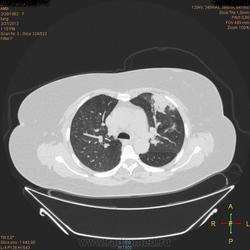

Здравствуйте, коллеги .Нужна помощь.Больная страдает Бронх.астмой.Беспокоять кашель,одышка , слабость, боль левой грудной клетке.Была температура 37,5- 38,0.Данный момент получает цефомизин темпер нормализовалось.Хочеть стационарное леч.Обратите пожалуиста на молочные железы, справа была операция год назад .Беспокоять боль правой мол.железе.

Во-первых, нет дайкомов. По представленным изображениям, изменения в левом легком дифференцировал бы между ТЭЛА мелких ветвей и организующей пневмонией, справа - пока вариантов нет (нужны дайкомы).

+1. Диф. диагностика между ОП и ТЭЛА обоих легких. Исключить ТЭЛА методом КТ с в/в боюсным контрастированием.